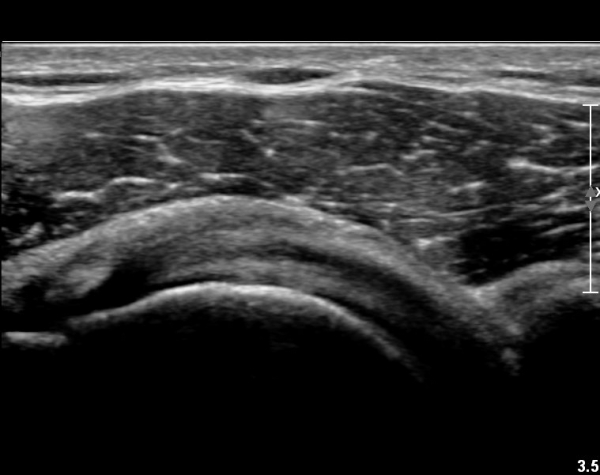

ŽÃËÀÚ¸¦ Á¶±Ý ´õ ¸»´Ü¹æÇâ(caudal)À¸·Î À̵¿ÇÏ´Ï ÆÄ¿­ÀÌ ´õ¿í ¶Ñ·ÈÇÏ´Ù(»çÁø 2, 3).